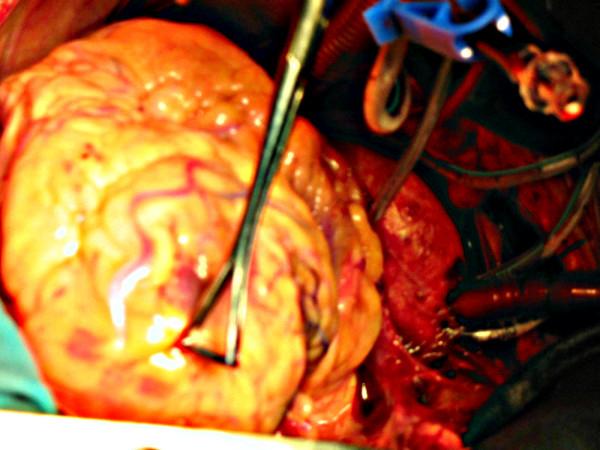

We describe, in a 61 year old man, with coexistent aortic stenosis, the anomalous origin of posterior descending artery (PDA) from a stenotic left anterior descending (LAD) artery, as its continuation across the left ventricular apex, in the presence of a normally arising and atretic proximal right coronary artery. The patient underwent mechanical aortic valve replacement and triple coronary artery bypass grafting and made an uneventful recovery. To the best of our knowledge, origin of PDA as a continuation of LAD across the left ventricular apex in the presence of a normally arising but atretic proximal right coronary artery has never been described in literature before. There is one previous case report of continuation of LAD as PDA across the left ventricular apex in a patient with single left coronary coronary artery with an absent right coronary ostium. As the blood supply to the entire interventricular septum is derived from this "hyperdominant" LAD system, stenosis of LAD can be catastrophic. A review of literature of the anomalies of right coronary artery and, in particular, of its anomalous origin from LAD and its coexistence with aortic stenosis, is presented.

我们描述了一名61岁患有主动脉瓣狭窄的男性患者,其右冠状动脉近端正常起源但闭锁,后降支动脉(PDA)异常起源于狭窄的左前降支动脉(LAD),并作为其延续穿过左心室心尖。该患者接受了机械主动脉瓣置换术和三支冠状动脉搭桥术,术后恢复顺利。据我们所知,在右冠状动脉近端正常起源但闭锁的情况下,PDA作为LAD的延续穿过左心室心尖的情况此前从未在文献中被描述过。之前有一例关于单支左冠状动脉且无右冠状动脉开口的患者中,LAD作为PDA延续穿过左心室心尖的病例报告。由于整个室间隔的血液供应都来自这个“优势过强”的LAD系统,LAD狭窄可能是灾难性的。本文对右冠状动脉异常,特别是其起源于LAD及其与主动脉瓣狭窄并存的文献进行了综述。